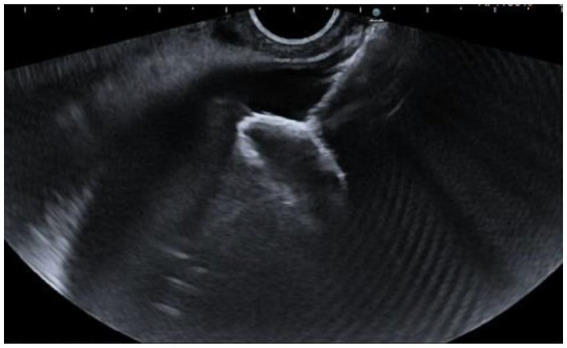

We used a slim, linear ultrasound endoscope (EG38-J10EGU, Pentax Medical, Germany) and the Arietta 70 ultrasound system. The transmural EUS-GBD approach involves placing a LAMS from the duodenum or stomach into the GB under EUS guidance (Figure 1), allowing, by the adherence of the GB to the gastrointestinal wall, the creation of a permanent fistulous tract (Figure 2).

The types of LAMS used were the Hot AXIOS stent (Boston Scientific, USA) or the Hot SPAXUS stent (Taewoong Medical, South Korea). The AXIOS stent sizes used were 15 mm × 10 mm and 10 mm × 10 mm, while the SPAXUS stent size was 16 mm × 20 mm.